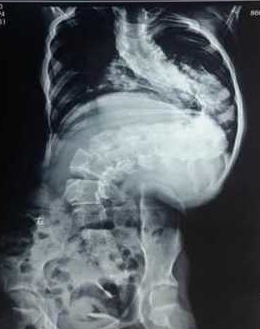

小婷婷今年13岁,十余年前无意间发现脊柱向侧后方弯曲,进行性加重,而且背部出现一个很大的罗锅畸形,曾去国内多家知名医院求医,终因风险及难度极大,而放弃治疗。后来打听到西安交大二院贺西京教授在治疗脊柱的疑难病、复杂病中有丰富的经验,慕名而来。小婷婷住院后,得到了贺西京教授、李浩鹏主任及治疗小组医护人员的关爱和重视。因患儿脊柱畸形严重,脊柱向外成角超过160度,而且胸廓畸形,心肺功能严重受影响,手术难度与风险极大,不宜直接做手术矫形。经专家讨论,先采用头颅及双下肢骨牵引术,将弯曲礓硬的脊体牵长、拉软。在持续牵引2周后,胸廓畸形、椎旁肌肉僵硬等情况得到较大改善。尽管这种牵引对患儿很痛苦,但得到了患儿及家长的理解和配合,为手术的顺利进行做好了准备。